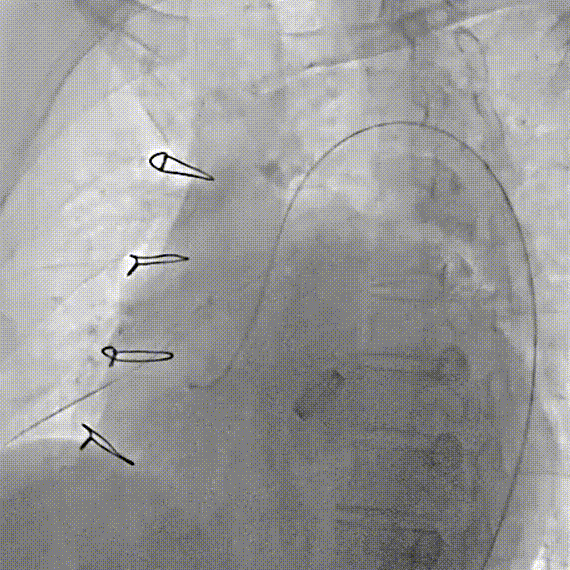

术中操作